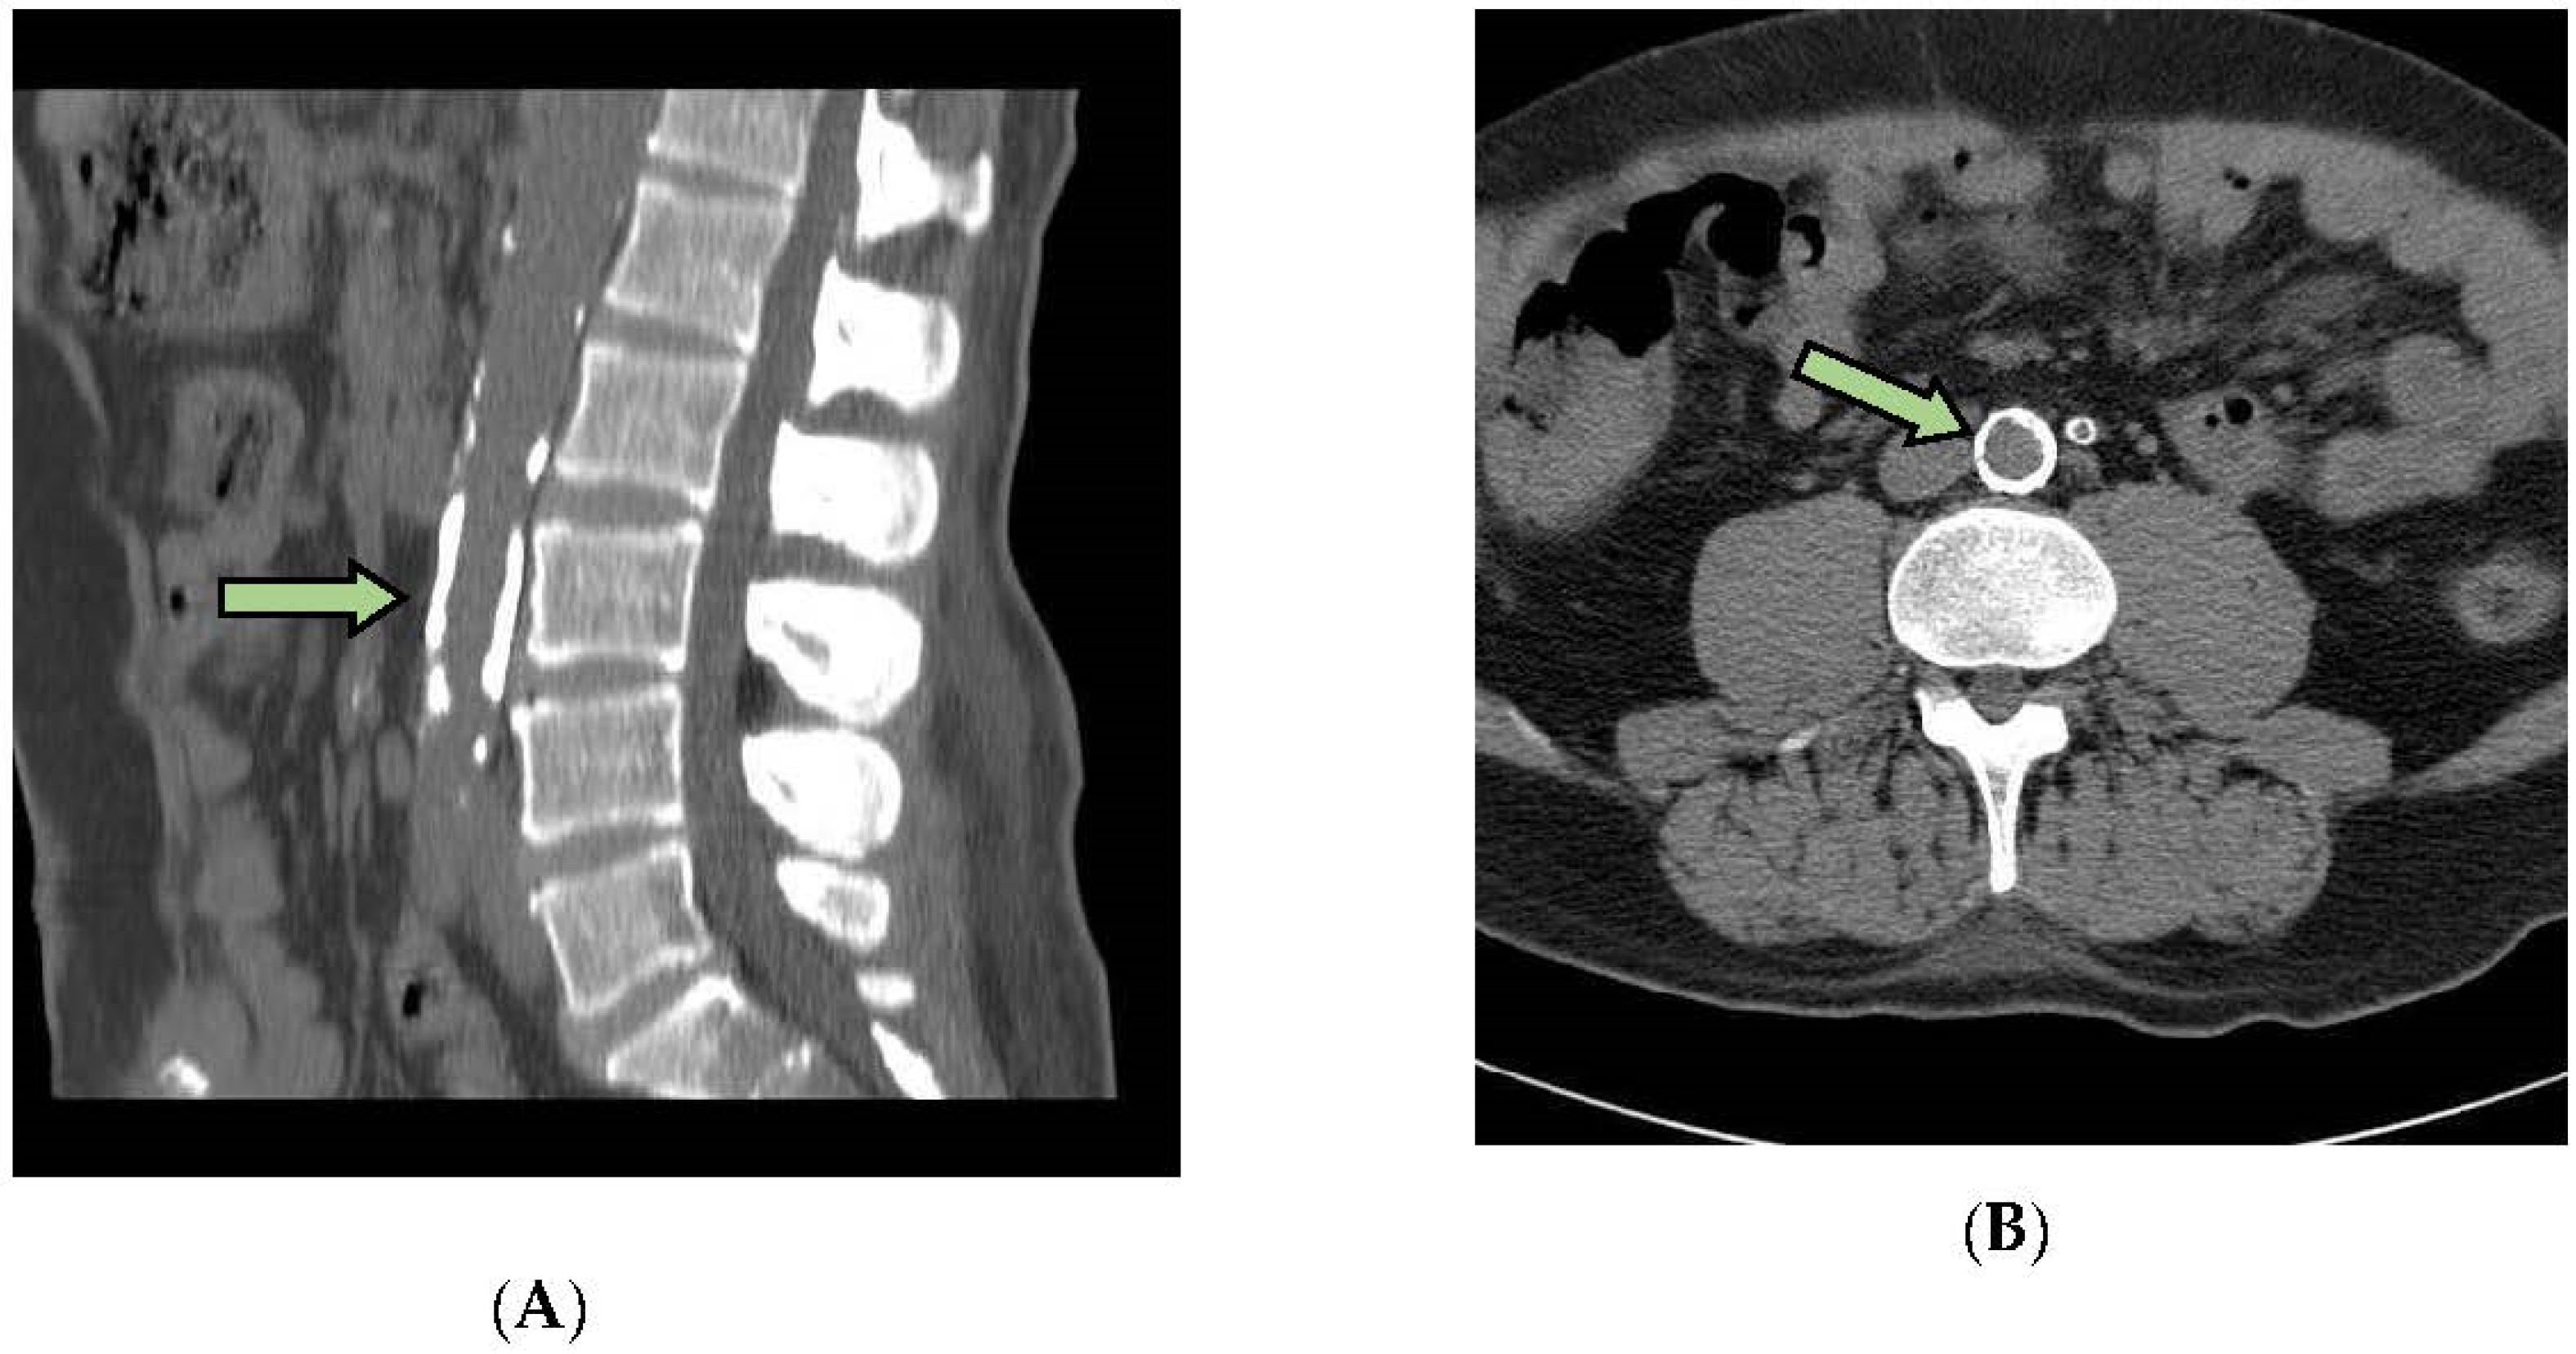

2.6. Measurement of Arterial Calcifications

2.7. Statistical Analysis